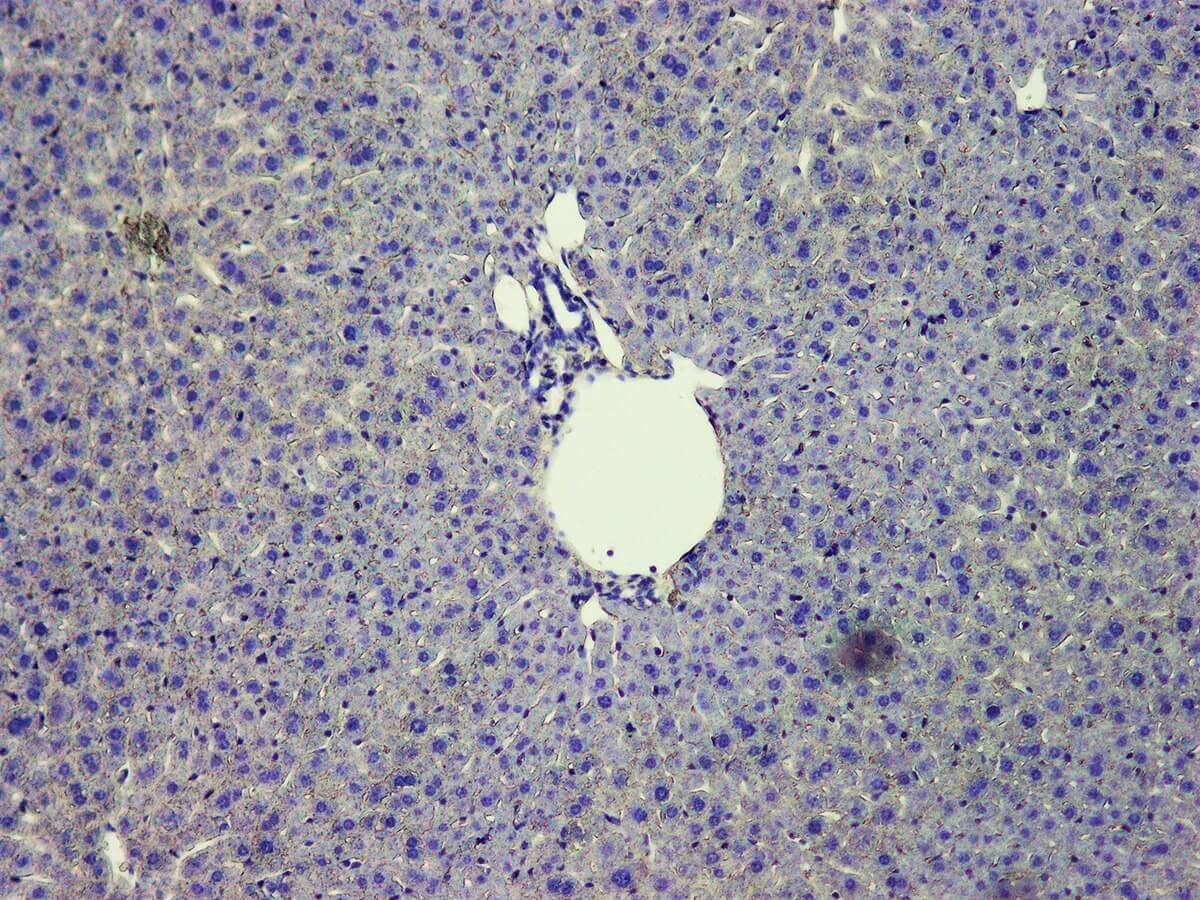

Hematoxylin is frequently used together with Eosin, nuclear fast red, periodic acid or alcian blue. It is also used in immunohistochemical procedures to visualize the end product. This product does not contain mercury.

KH07003-Harris-H-Lung-10-x.jpg     KH07003-Harris-H-Liver-10-x.jpg

Nuclei can be visualized as blue-purple.